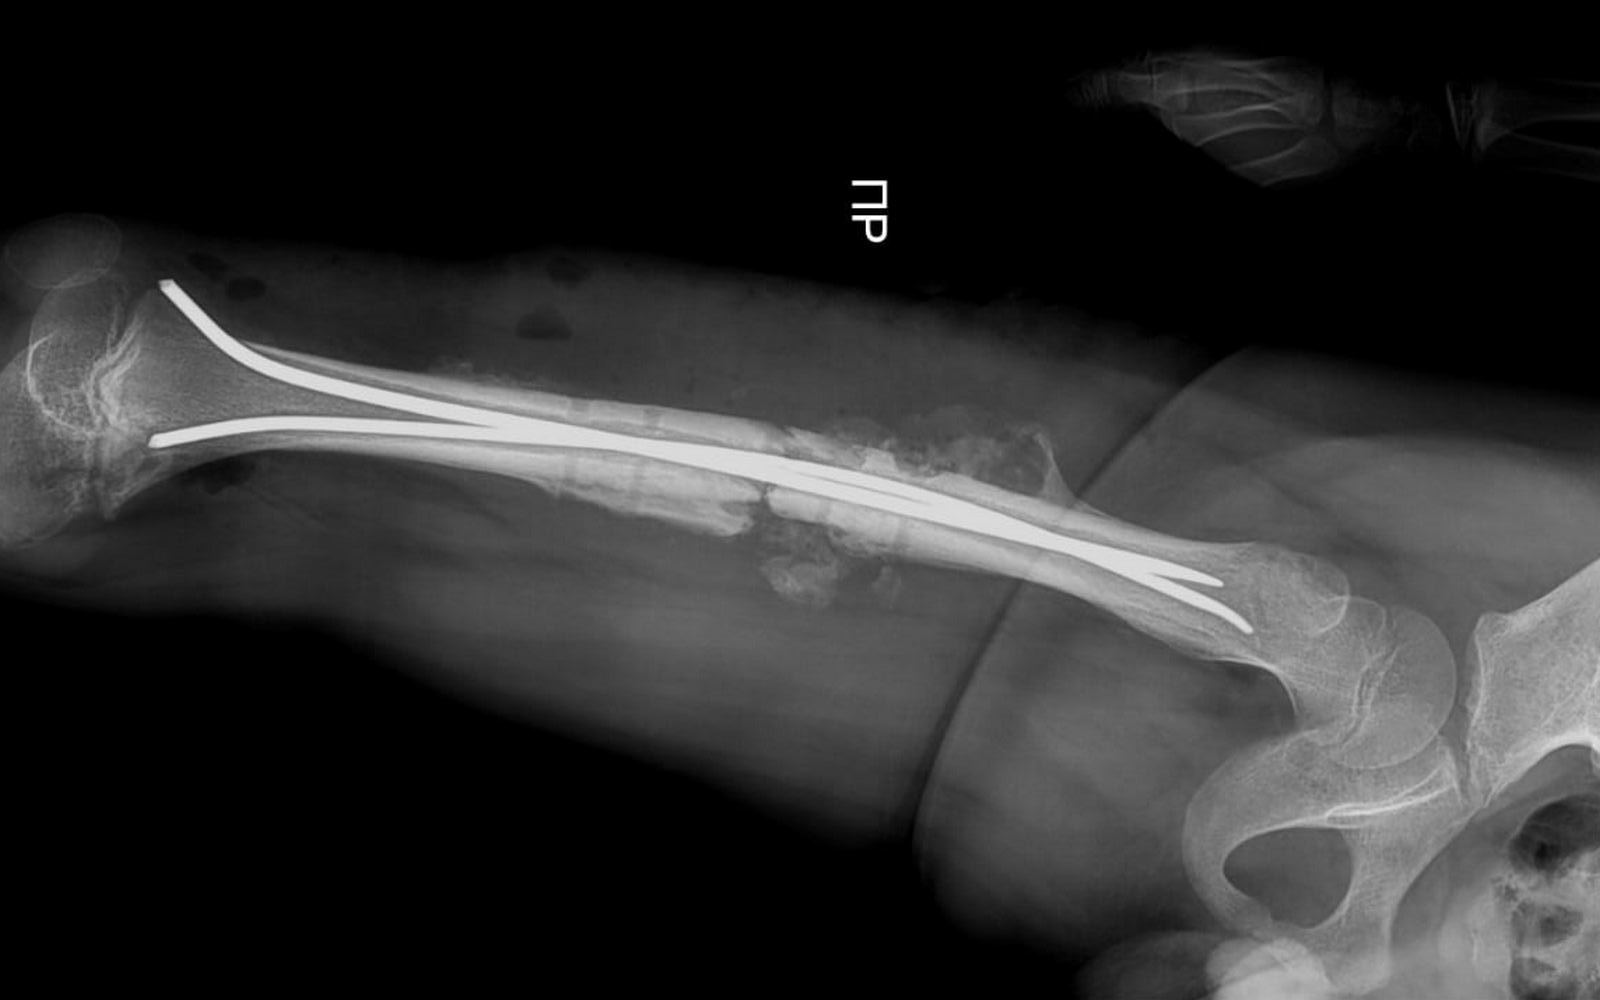

В стенах областной детской больницы впервые была проведена операция по установке гибких фиксирующих стержней, рассказал актауский общественник Азамат Сарсенбаев.

В августе этого года, по словам Азамата Сарсенбаева, ребёнка сбила машина. У мальчика сломалась кость.

Тогда на базе детской больницы в области бедра ему установили металлические фиксаторы.

На этой неделе мальчик неудачно упал и у него, к сожалению, сломались фиксаторы.

Врачам на этот раз пришлось повторно проводить операцию.

В течение часа детский хирург Курман Кайранов успешно заменил металлический на более современный гибкий стержень.

- Преимущество гибкого стержня заключается в том, что теперь при переломах больше не требуется делать большие разрезы в конечностях для установки фиксирующих стержней. Достаточно лишь сделать разрез в один сантиметр и вводить гибкий стержень под рентгеновским контролем, - рассказал Курман Кайранов.